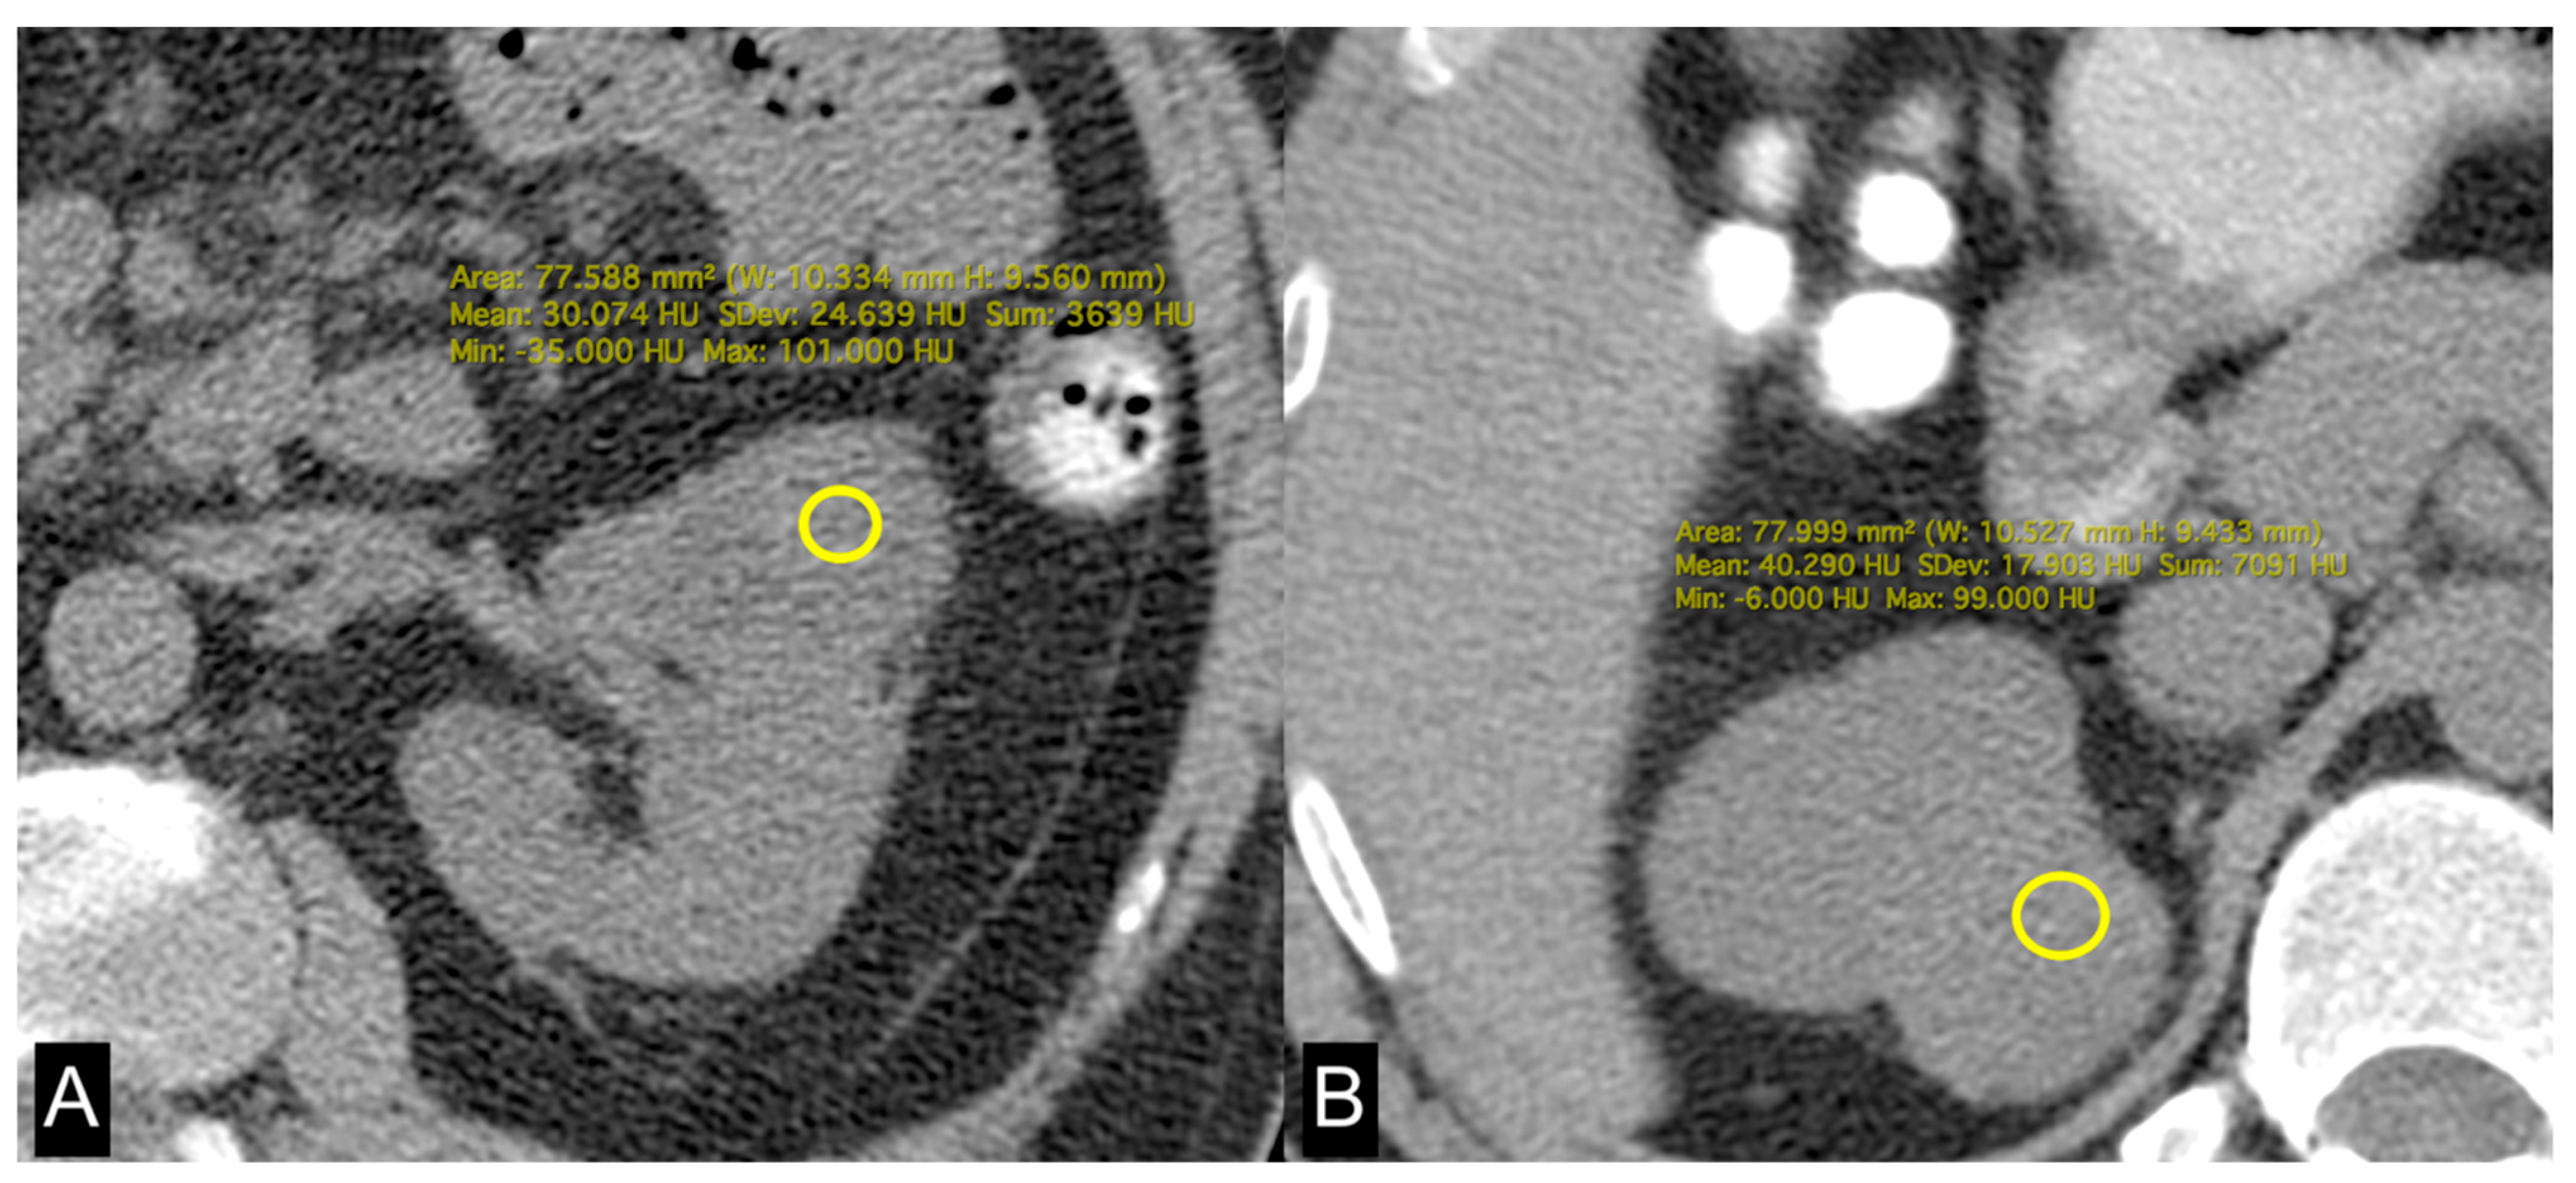

Figure 4.

Unenhanced axial CT images of patients with low-grade ccRCC with ADFP expression (A) and high-grade ccRCC with ADFP expression. (B) Yellow ROIs with different mean attenuation values of tumoral HU (HU: 30 and 40,2, respectively).

In this study, we evaluated the CT features of ADFP expression in ccRCC patients. A significant correlation was found with hydronephrosis (p = 0.025) (Figure 2). Furthermore, greater quantities of TAT, VAT, and SAT were found in low-Fuhrman-grade ccRCC patients with ADFP expression compared to high-Fuhrman-grade ccRCC patients with ADFP expression (p = 0.004, p = 0.003 and p = 0.045, respectively) (Figure 3). Significantly lower tumoral HU values were found in low-Fuhrman-grade ccRCC patients with ADFP expression compared to high-Fuhrman-grade ccRCC patients with ADFP expression (p = 0.002) (Figure 4), and significantly lower values of tumoral HU in low-Fuhrman-grade ccRCC patients without ADFP expression were found compared to high-Fuhrman-grade ccRCC patients without ADFP expression (p = 0.021).

Yao et al. found that low-grade ccRCCs tend to exhibit higher expression levels ADFP, which plays a role in fatty acid uptake and the formation of lipid droplets within cells, compared to high-grade tumors The overexpression of ADFP is associated with increased intracellular lipid storage in low-grade ccRCCs relative to high-grade tumors [9,35]. Choi et al. demonstrated that the decreased attenuation detected in low-grade tumors on unenhanced CT images is likely indicative of a higher lipid content within these tumors [36].

Consistent with these findings, we observed higher abundances of TAT, VAT, and SAT in low-Fuhrman-grade ccRCC patients expressing ADFP compared to high-Fuhrman-grade ccRCC patients with ADFP expression. Additionally, we noted significantly lower tumoral HU values in low-Fuhrman-grade ccRCC patients expressing ADFP compared to high-Fuhrman-grade ccRCC patients expressing ADFP (p = 0.002), as well as significantly lower HU values in low-Fuhrman-grade ccRCC patients without ADFP expression compared to high-Fuhrman-grade ccRCC patients without ADFP expression (p = 0.021). This explains how the excessive amount of adipose tissue determines an increase in HIF with associated greater expression of ADFP and a consequent increase in intracellular lipid droplets; the relationship between HIF and ADFP could be further strengthened by VHL gene mutation, which inactivates HIF degradation.